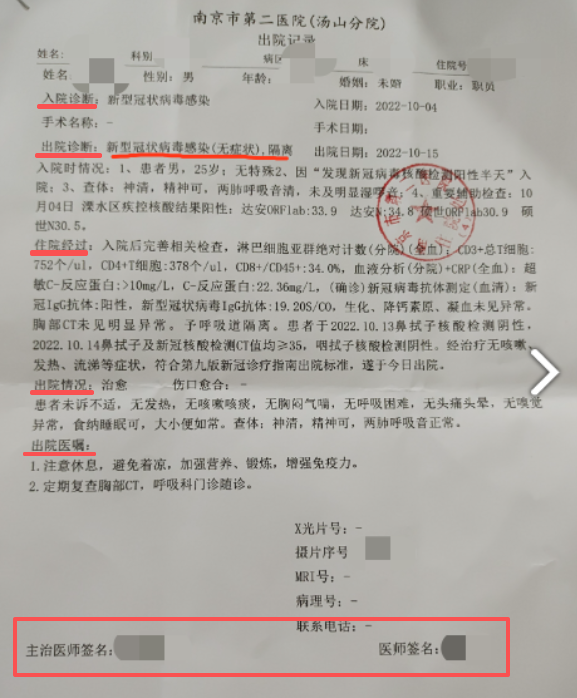

1929年10月汪精卫才从法国回香港,中医骗那是张嘴就谎啊,还张嘴就汪精卫掌实权,汪精卫1929年10月回来是支持第二次蒋桂战争干老蒋的,他还掌实权。 中医骗的特点就是张嘴就喷谎。主打一个我虽然小学3年级文化,但是够我骗文盲。 1929年,弗莱明刚刚发明抗生素,还只是实验室与论文,这就跑中国来了? 1929年,面对细菌性痢疾,西医就是没有办法治疗,所以就说治不了。1929年弗莱明虽然已经发明青霉素,但是产量感人,当时第一次使用对一个受伤感染的警察,非常有效,但是手中的一点青霉素用完了,于是警察还是shi了。 所以,西医诚实的说,没有办法治疗。 而诚实,是一种多么宝贵的品质。 因为你诚实,你说出来:我不能治疗,那么,这个疾病,就有了解决了一半。 因为你以后,所有的西医,西药,医疗器械从业者,都会想尽办法去攻克这个疾病。 而多少的绝症,曾经的绝症,因为西医的诚实,而最终研究出了真正治疗办法。 例如1921年的胰岛素。 例如1929年的青霉素。 例如1998年的伟哥。 例如2006年的HPV疫苗。 你没有。 3、西医不仅是个自然科学,他还是个管理秩序。 没有人敢保证每个西医从业者都会履行自己的诺言,所以西医除了希波克拉底誓言,还双管齐下,有一套完整的制度。 1)、一人为私,二人为公。西医的任何重大治疗与决策都是多人完成。 手术有术前评估,有术前讨论。 化验师管理体系是单独的。检查技师管理体系是单独的。甚至护士也是单独独立的。护士只是执行医生的医嘱,只是工作关系,不是上下级。护士的管理也是独立的,不归医生管理。麻醉师的管理也是独立的。 而这么多的独立,就是垂直管理,在根子上就切断医生自己一手遮天的可能。 2)、完善的文档记录。 住院病例保存30年。 住院病例需要上级医生签名。需要三级签名。修改需要红笔。 交病案后就归病案室,医生是要不回来了的。因为病案室也是独立的。 出院一定会给出院小结。需要全病历的也可以,掏复印费去病案室复印,所有的医院都允许。 所以很多中医骗张嘴就是他啥病西医看不好去找中医一看就好了,我就让他发出院小结,结果没有一个发的。我不要你隐私,你把你个人隐私涂掉,我就要病案。没有,全闪了。 等等。 在网上随便找点: |

一份最简单的住院小结,而且是格式化的,入诊、出诊、入情、治经、出情、医嘱,是格式化的,医生根本就删不掉。 送礼物 还没有人送礼物,鼓励一下作者吧 |